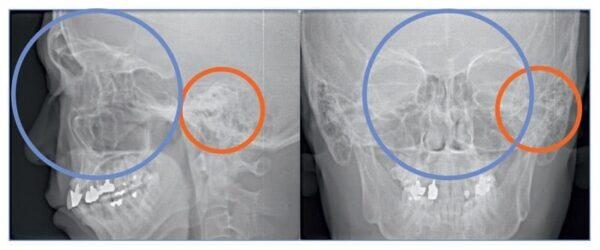

- Chỉnh nha: phân tích 3D toàn hàm, răng ngầm, bất đối xứng xương

- Đánh giá TMJ: hình ảnh lồi cầu 3D, không gian khớp